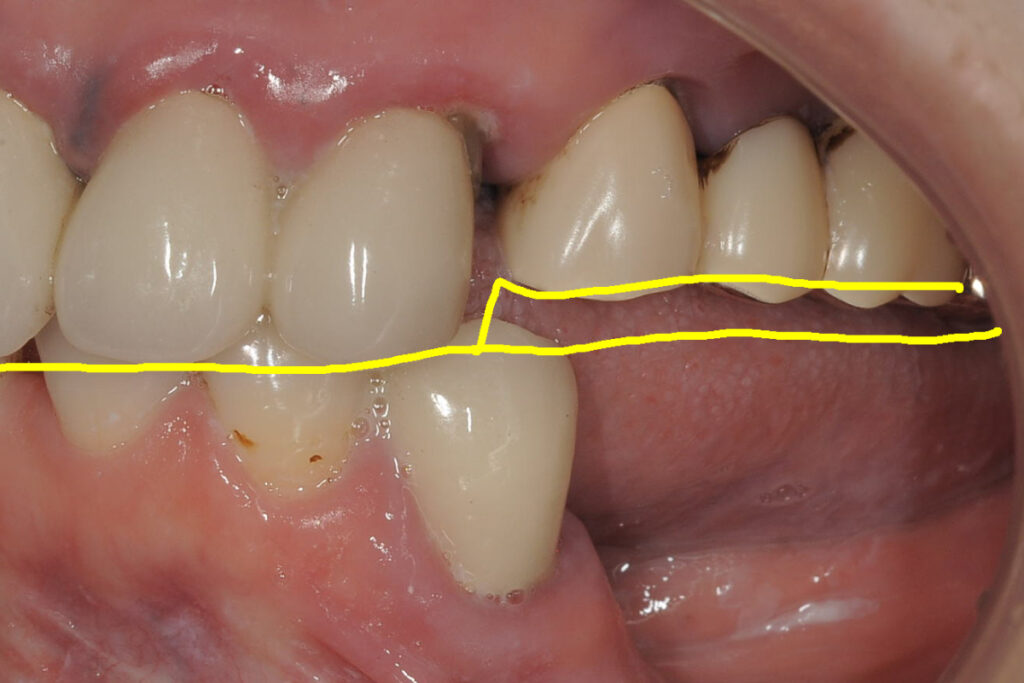

症例1|骨量不足で断られたケース

――「骨が足りない」というNOを、どう再定義したか

50代女性。下顎奥歯の欠損。片側咀嚼が続き、噛み合わせ全体への不安が強まっていました。他院でインプラント相談を行いましたが、「骨量が足りないため難しい」と説明され、治療を断念しました。

■当院での判断

吉留英俊が行ったのは、「できるかどうか」ではなく、「成立させた場合に安定するかどうか」の検討です。

- 骨造成(GBR)を併用した場合の骨の獲得量の見込み

- 咬合負荷の方向(どの方向に力がかかるか)と分散の設計

- 術後管理を継続できる条件(通院、清掃、生活習慣)

これらを精査した結果、条件付きでできると判断しました。

■選択した治療

- 骨造成(GBR)を併用したインプラント治療

■結果としての状態

治療は完遂しました。現在は定期管理下で、機能的・構造的に安定した状態を維持しています。患者の実感は「噛める」だけではありません。「これ以上悪化させないで済む」という安心が残りました。